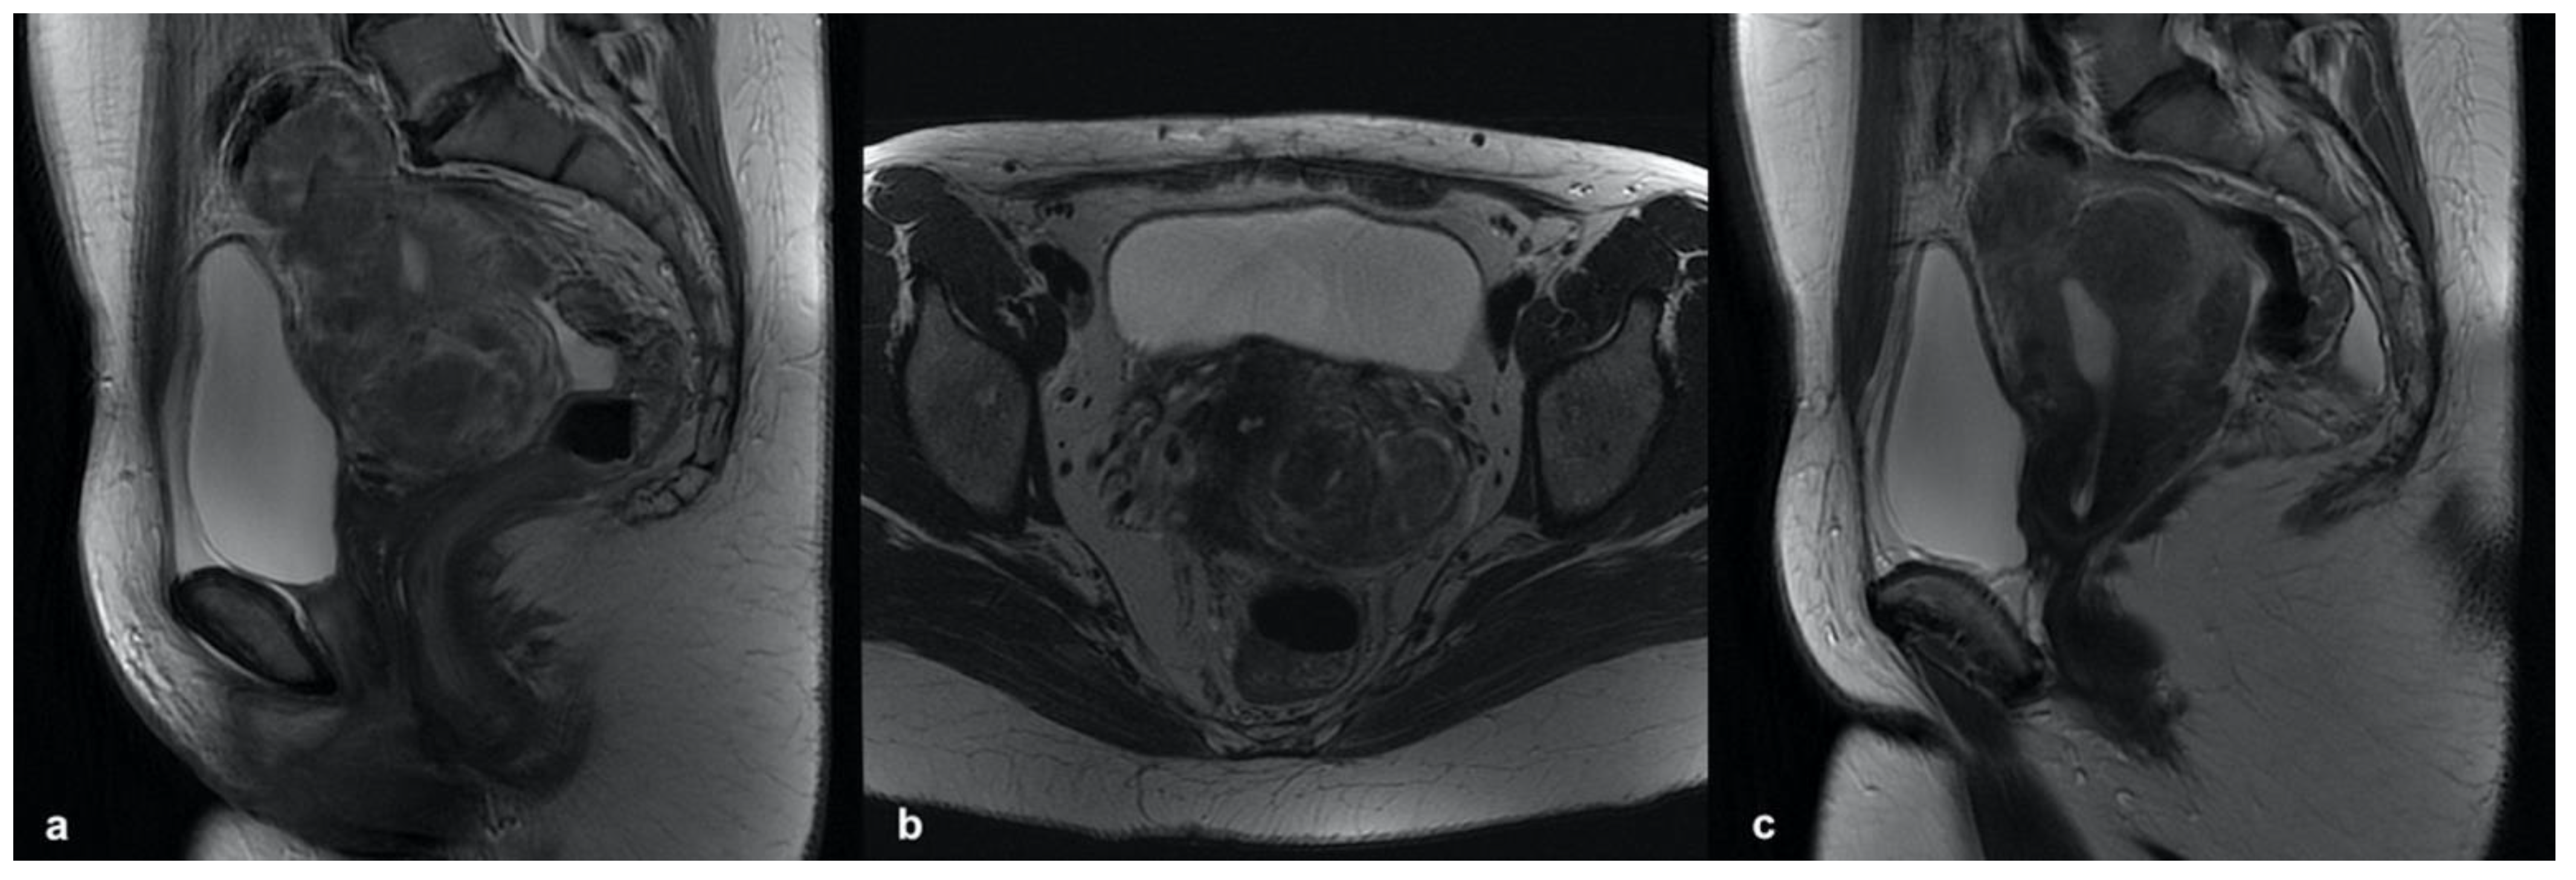

3.5.1. Leiomyoma

3.5.4. Low-Grade Endometrial Stroma Sarcoma (LG-ESS)